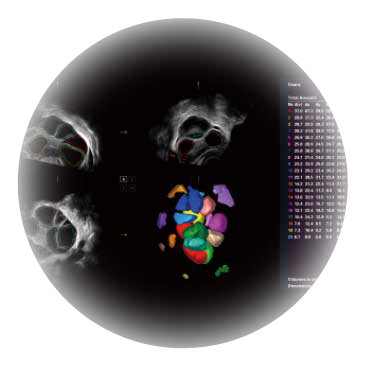

可同时显示组织结构表面和内部的轮廓信息,达到透视效果,为临床提供更丰富的诊断信息。

卵泡结构的自动识别和测量,可显示多组测量数据。

大角度腔内容积探头,可完整包络子宫及盆底结构,充分展示组织结构毗邻关系。